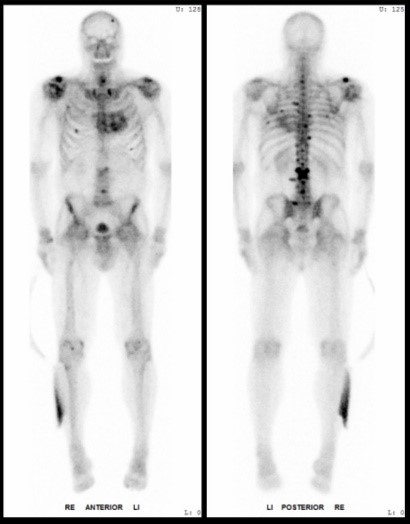

Inteventionelle Radiologie-Teil der Diagnostischen Radiologie oder ein eigenständiges Fachgebiet?

Die Entwicklung und Integration der interventionellen Radiologie im klinischen Alltag wird weltweit unterschiedlich gehandhabt. Während sie in den USA bereits als eigenständiges Fachgebiet anerkannt ist, gilt sie in Deutschland nach wie vor als fakultatives Teilgebiet innerhalb der Radiologie.

In der interventionellen Radiologie beschränkt sich die Tätigkeit des Radiologen nicht allein auf die bildgebende Diagnostik. Vielmehr übernimmt er eigenständig minimalinvasive Eingriffe und trägt dabei die Verantwortung für die prä-, peri- und postoperative Versorgung der Patient: innen.

Mit diesem Wahlfach möchten wir Ihnen praxisnahe Einblicke in das vielseitige und verantwortungsvolle ärztliche Arbeiten in der interventionellen Radiologie ermöglichen.